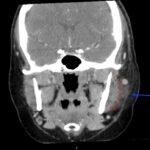

A 36-year-old immunocompetent female presented to the emergency department (ED) with five days of headache and left-sided facial pain. Physical exam showed conjunctival injection of the left eye with multiple vesicular lesions distributed along the V1 dermatome. Labs were remarkable for mild elevation in erythrocyte sedimentation rate (ESR) and c-reactive protein (CRP) with no elevation in white blood cell (WBC) count. Computed tomography (CT) with contrast of the neck revealed soft tissue stranding around the parotid gland. The patient was diagnosed with herpes zoster ophthalmicus (HZO) with concurrent ipsilateral parotitis and subsequently treated with valacyclovir, ofloxacin eye drops, topical erythromycin ointment and amoxicillin/clavulanic acid. Upon follow-up ten days after discharge, the patient noted marked improvement in her symptoms and reduction in pain. To our knowledge, this is the first case described in medical literature of a female patient with HZO and ipsilateral parotitis.